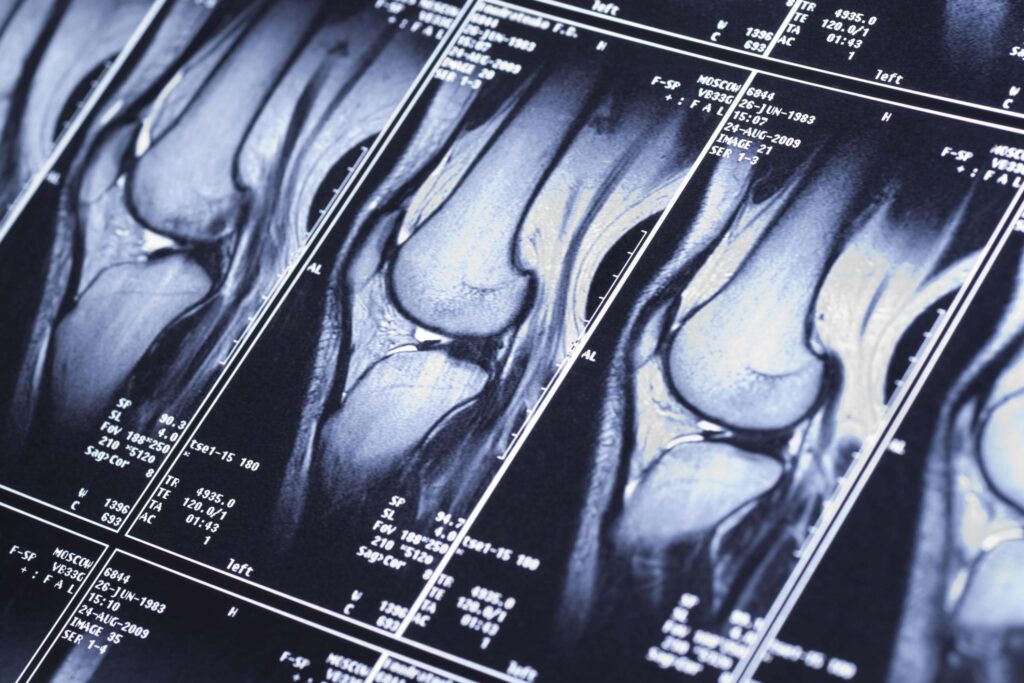

МРТ суставов в Харькове

Магнитно-резонансная томография (МРТ) суставов – это метод исследования, который позволяет получить детальные изображения суставов, мягких тканей и костей без использования рентгеновских лучей. В отличие от КТ суставов при МРТ используются сильные магнитные поля и радиоволны для создания снимков срезов тканей в разных проекциях.

Сделать МРТ суставов в Харькове можно в Европейском Радиологическом Центре. В ЕРЦ можно пройти МРТ-диагностику локтевого, лучезапястного, плечевого, коленного, голеностопного и тазобедренного суставов с контрастом и без него.

МРТ коленного сустава

МРТ коленного сустава помогает выявить повреждения связок (например, передней или задней крестообразной связки), разрывы менисков, воспаление сухожилий, износ хрящевой ткани при артрите. Магнитно-резонансная томография также показывает наличие опухолей, воспалительных процессов в суставах (синовит), скопление жидкости (выпот), патологические изменения, которые могут быть пропущены на обычных рентгеновских снимках.